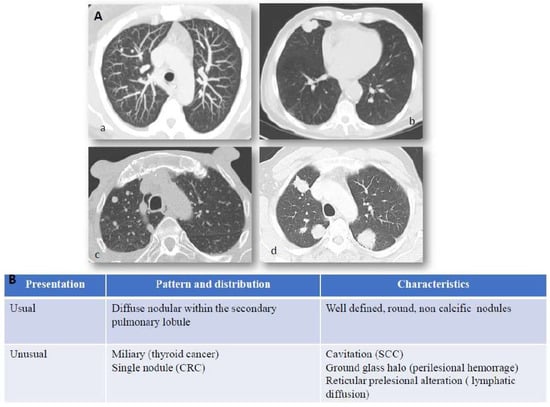

2. Clinical and Radiological Presentation of Pulmonary Metastases